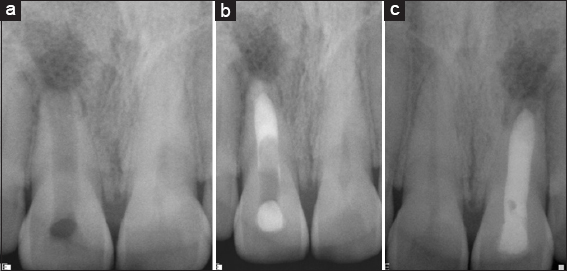

Group I: (Mineral trioxide aggregate apexification)

The procedure of MTA Apexification was carried out as follows: Under Rubber dam isolation, access preparation was done in necrotic immature permanent teeth of all the 36 subjects. Canals were copiously irrigated with 2.5% sodium hypochlorite, and minimal instrumentation was done to prevent the weakening of the lateral dentinal walls. Triple antibiotic paste (TAP) was placed as an inter-appointment medicament in the dried canals, and the coronal access was sealed with intermediate restorative material for 4 weeks. During the visit of patients after 4 weeks under rubber dam isolation, TAP was removed from the canal using irrigation with 2.5% sodium hypochlorite. Canals were dried and following the procedure was carried out [Figure 1a-c].

thumb

Figure 1: (a) Preoperative, (b) Mineral trioxide aggregate apexification, (c) Follow up 1 year

In Group I, MTA was placed in the canal using messing gun to form the 3–4 mm of apical plug. It was obturated using gutta-percha and AH Plus sealer. The tooth was permanently restored with adhesive restoration in the same visit.